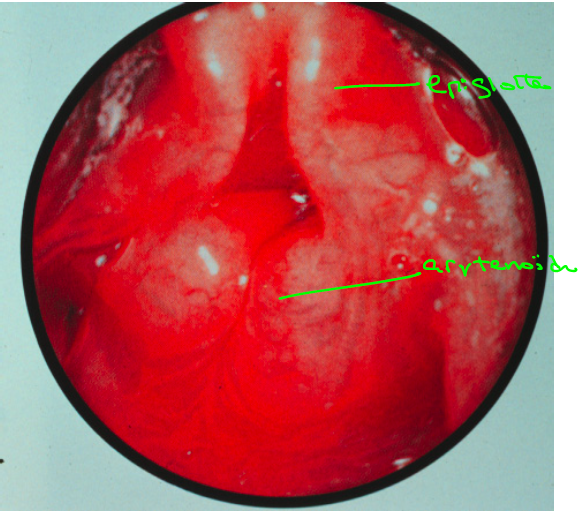

Que faut-il évaluer dans une laryngoscopie indirecte?

Il faut évaluer plusieurs éléments:

On doit noter les changements de coloration, les changements de structure, les sécrétions (en particulier un éventuel “pooling” dans le sinus piriforme) et bien sur, la mobilité des cordes vocales.

Les cordes vocales sont habituellement pâles, lisses, les bords libres sont bien réguliers, le reste de la muqueuse est lisse et rosée.